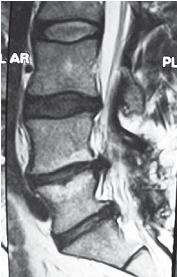

Следующий пример показывает состояние поясничного отдела позвоночника через два года после проведённой ламинэктомии. Ламинэктомия (лат. lamina — пластинка, греч. ektome — иссечение) — хирургическая операция: вскрытие позвоночного канала путём удаления дуг позвонков.

На МРТ №°103 наблюдается грыжа межпозвонкового диска в сегменте LIV-LV, частично компенсированная спондилёзом, гипертрофия задней продольной связки и выраженный эпидурит на данном уровне. В сегменте LV-SI наблюдается протрузия межпозвонкового диска, компенсированная спондилёзом. На уровне этих же сегментов наблюдается рубцовоспаечный процесс, как следствие перенесённой хирургической операции — ламинэктомии, проведённой в сегментах (LIV-LV, LV-SI), с целью устранения грыжи межпозвонковых дисков и декомпрессии спинномозговых корешков на данных уровнях.